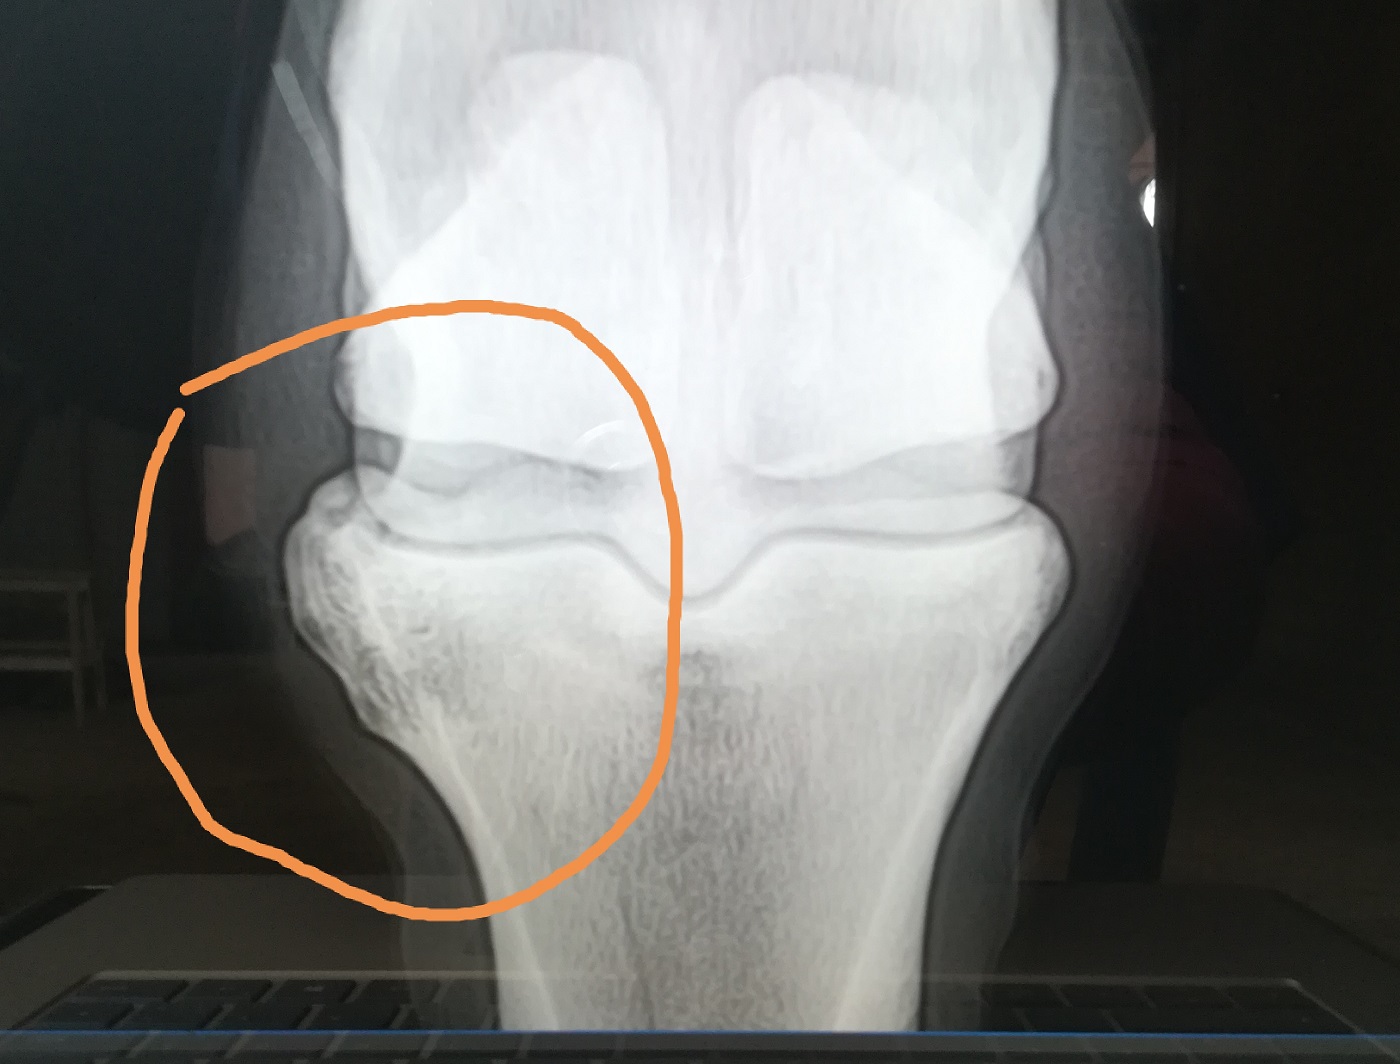

nach 17 Monaten tolles reiten bei mir und meinem vierbeinigen Freund, haben wir eine neue Baustelle: Knochenzubildung bzw Arthrose im Fesselgelenk außen am Hinterbein

inkl. Fesselgelenksentzündung , was wohl ohne dem nicht geht